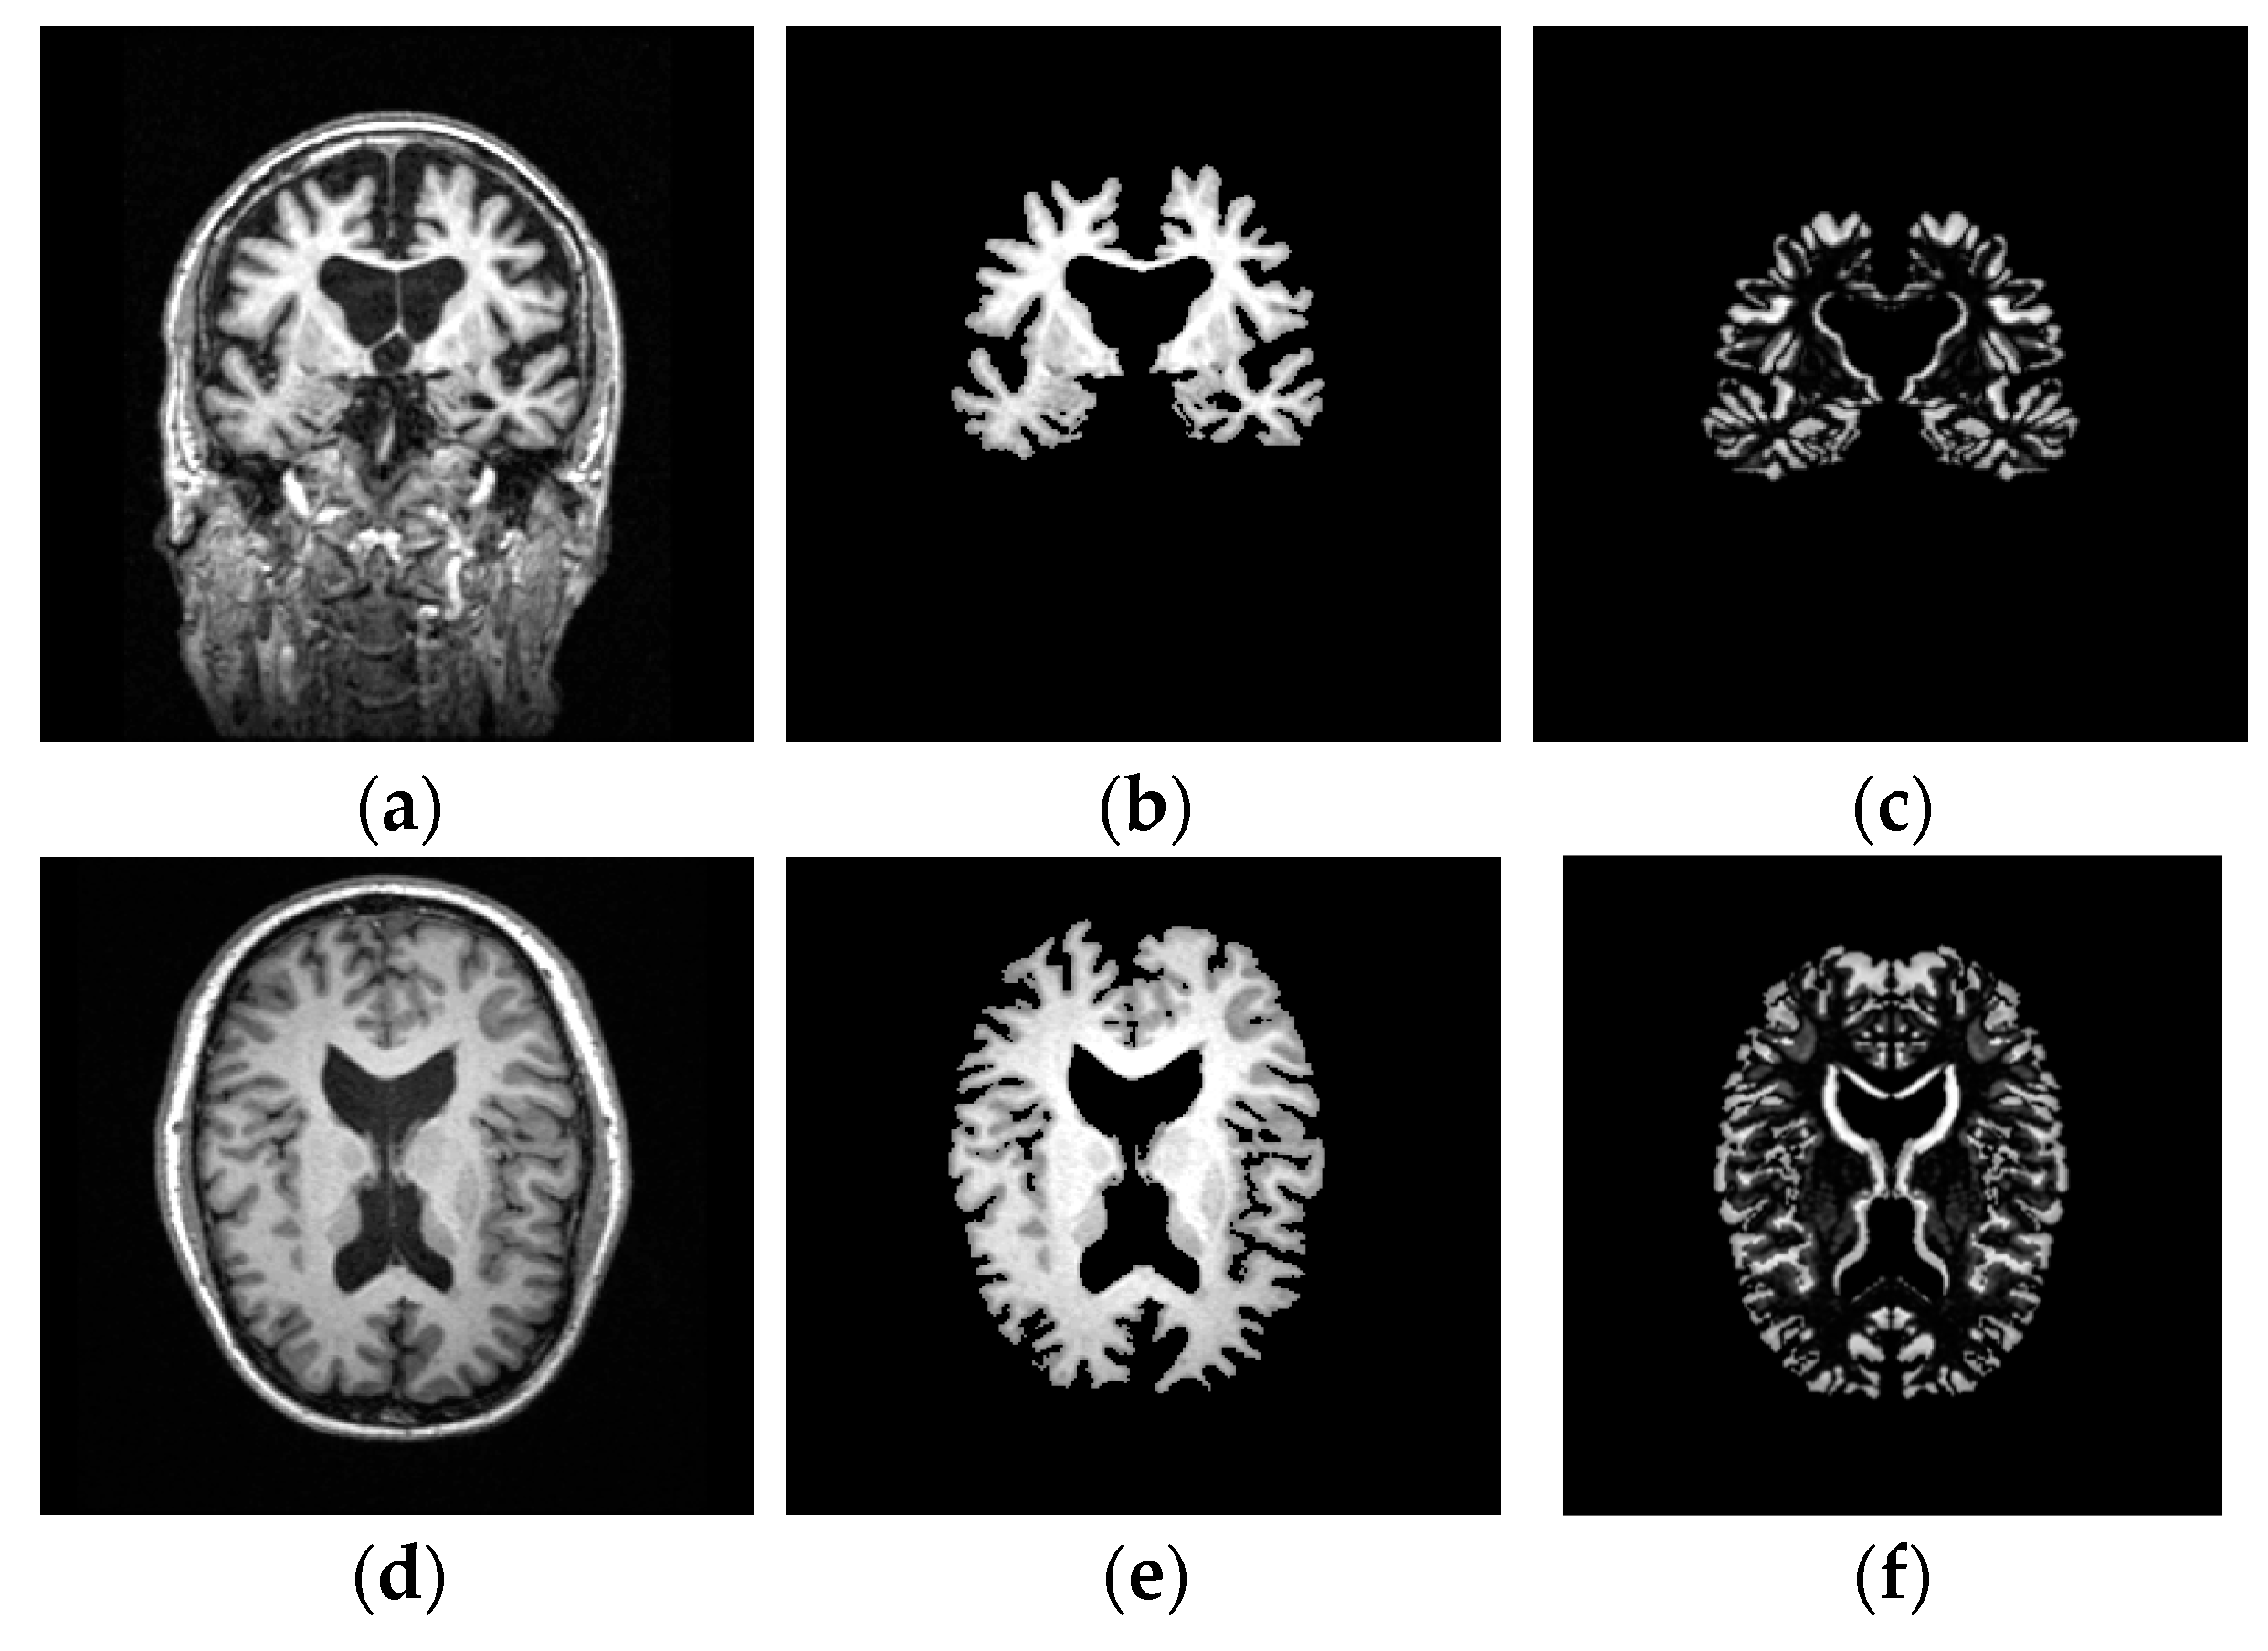

3.2.1. Image Preprocessing